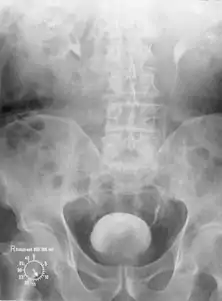

После открытия в 1895 году Вильгельмом Рентгеном рентгеновского излучения возникает рентгенология, превращающаяся позднее в раздел радиологии. Первое применение рентгенологии в урологической диагностике относится к 1927 году, когда контрастное вещество через катетер было введено в мочевой пузырь и почечную лоханку пациента, после чего была получена первая цистограмма и пиелограмма с изображением органов мочевыделительной системы.